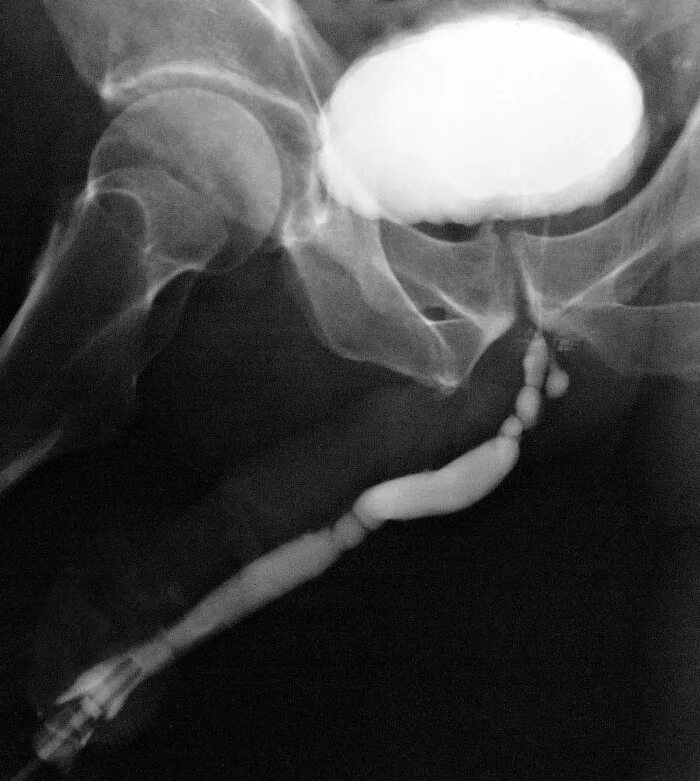

Ощущение в мочеиспускательном канале